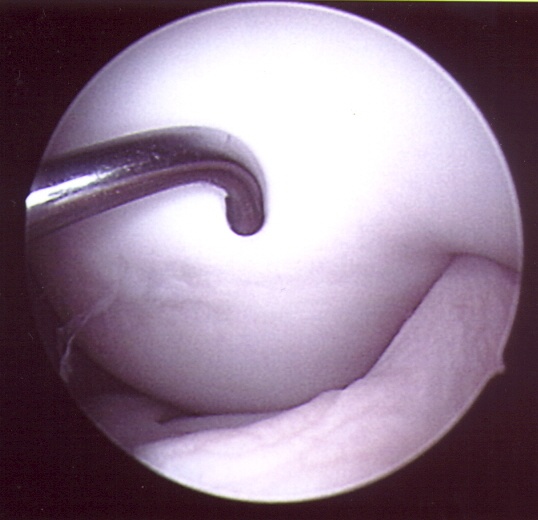

Knorpelschäden machen in der Regel Beschwerden, wenn lockere Anteile sich frei im Gelenk bewegen und ein loser Übergang zwischen intakten Knorpel gewissermaßen als Knorpelauf-werfung entsprechende Störungen verursacht. Um den ständigen Anfall von Knorpelabrieb im Gelenk zu stoppen, müssen die aufgebrochenen, aufgefransten und bröckligen Knorpeloberflächen geglättet werden. Hierzu stehen besondere motorgetriebene Werkzeuge zu Verfügung. Ein Wiederaufbau des defekten Knorpels ist nur sehr bedingt möglich.

Bei jungen Patienten kann mit einer sogenannten Anbohrung des Knochens erreicht werden, daß sich ein Ersatzknorpel im Laufe der Zeit an der entsprechenden Stelle wieder bildet, jedoch ist dieser nur sehr begrenzt belastungsfähig.